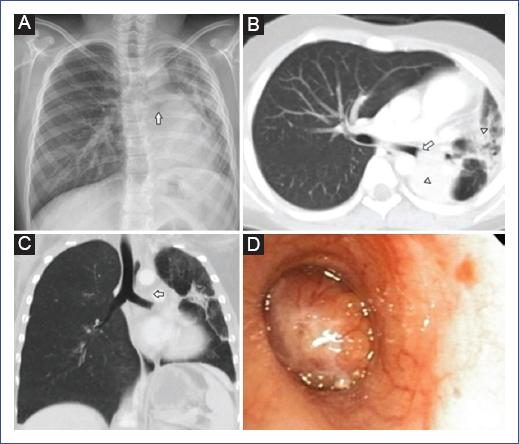

En la radiografía de tórax se observó una opacidad retrocardiaca que impresionaba seccionar el bronquio principal izquierdo, infiltrados heterogéneos y leve disminución del volumen del pulmón izquierdo (Fig. 1A). La tomografía computarizada con contraste reveló una masa redondeada de densidad heterogénea de 39 × 33 × 40 mm, cuyo epicentro se localizaba entre la aorta descendente y rama interlobar izquierda del tronco de la pulmonar. Dicha masa se extendía hacia el interior del bronquio principal izquierdo obstruyendo completamente su luz, condicionando atelectasia total del lóbulo inferior izquierdo y atelectasia parcial del lóbulo superior izquierdo (Fig. 1 B y C). En la broncoscopia flexible se observó una masa endobronquial con oclusión total del bronquio principal izquierdo (Fig. 1D). Se realizó biopsia transtorácica con aguja tru-cut guiada por ecografía, con un resultado sugestivo de tumor de tipo glándula salival.

Figura 1 Carcinoma mucoepidermoide pulmonar izquierdo en un niño de 9 años con hemoptisis recurrente. A: la radiografía de tórax posteroanterior muestra opacidad retrocardiaca izquierda con un corte abrupto del bronquio principal izquierdo (flecha), infiltrados heterogéneos y disminución del volumen pulmonar izquierdo. B: imagen axial de la tomografía de tórax con contraste que muestra una masa endobronquial (flecha) que ocluye totalmente el bronquio principal izquierdo, áreas irregulares de alta densidad en segmentos de la língula y lóbulo inferior izquierdo en relación con atelectasia (puntas de flecha). C: la reconstrucción multiplanar coronal muestra una masa dentro del bronquio principal izquierdo (flecha), con disminución del volumen pulmonar izquierdo. D: la broncoscopia muestra tumor polipoide endobronquial con vascularidad, ocluyendo completamente el bronquio principal izquierdo.

El estudio de imágenes inicial como la radiografía y la tomografía es importante para diferenciar de otras enfermedades8. En esta se puede observar la masa que obstruye la luz bronquial11, atelectasias9, y la localización y extensión de la tumoración12. En nuestro paciente la tomografía permitió identificar la masa en el bronquio principal izquierdo y su extensión hacia los lóbulos superior e inferior izquierdo (Fig. 1C). Una serie de 45 adultos con esa neoplasia reportó una mayor ubicación en los lóbulos superior e inferior izquierdo12, y otra revisión de 145 casos en niños reportó mayor frecuencia de localización en pulmón izquierdo8. La localización del tumor en nuestro paciente es concordante con esas series grandes.